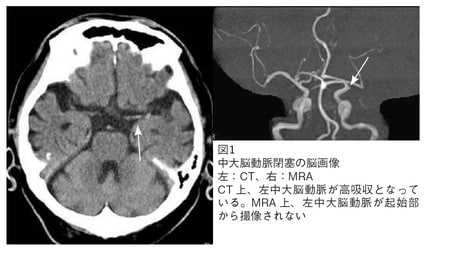

1例目(図表1)は70代後半の男性。突然の意識障害と右片麻痺で発症しました。既往歴として心房細動があります。

発症後1時間の単純CT検査にて、左中大脳動脈水平部に一致した高吸収値陰影(矢印)を認めますが、対側もやや高吸収値のため判断が難しく、左中大脳動脈の方がより高い(白色)ようです。MRA検査にて左中大脳動脈閉塞(矢印)と明瞭に診断できました。この患者さんは急性期を脱し、回復期リハビリテーション病棟で右片麻痺と失語症のリハビリを受けて在宅復帰されました。